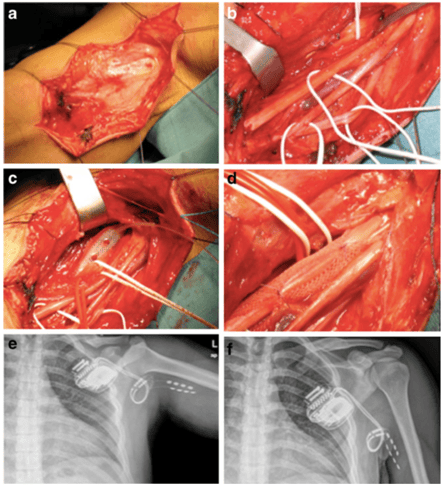

La référence Stevanato G, Devigili G, Eleopra R, Fontana P, Lettieri C, Baracco C, Guida F, Rinaldo S, Bevilacqua M (2014) Chronic post-traumatic neuropathic pain of brachial plexus and upper limb: a new technique of peripheral nerve stimulation. Neurosurg Rev. : 10.1007/s10143-014-0523-0 L'article L'objectif de cette étude était d'évaluer le soulagement de la douleur chez des patients souffrant de douleur neuropathique liée à un traumatisme du plexus brachial par la stimulation de la...